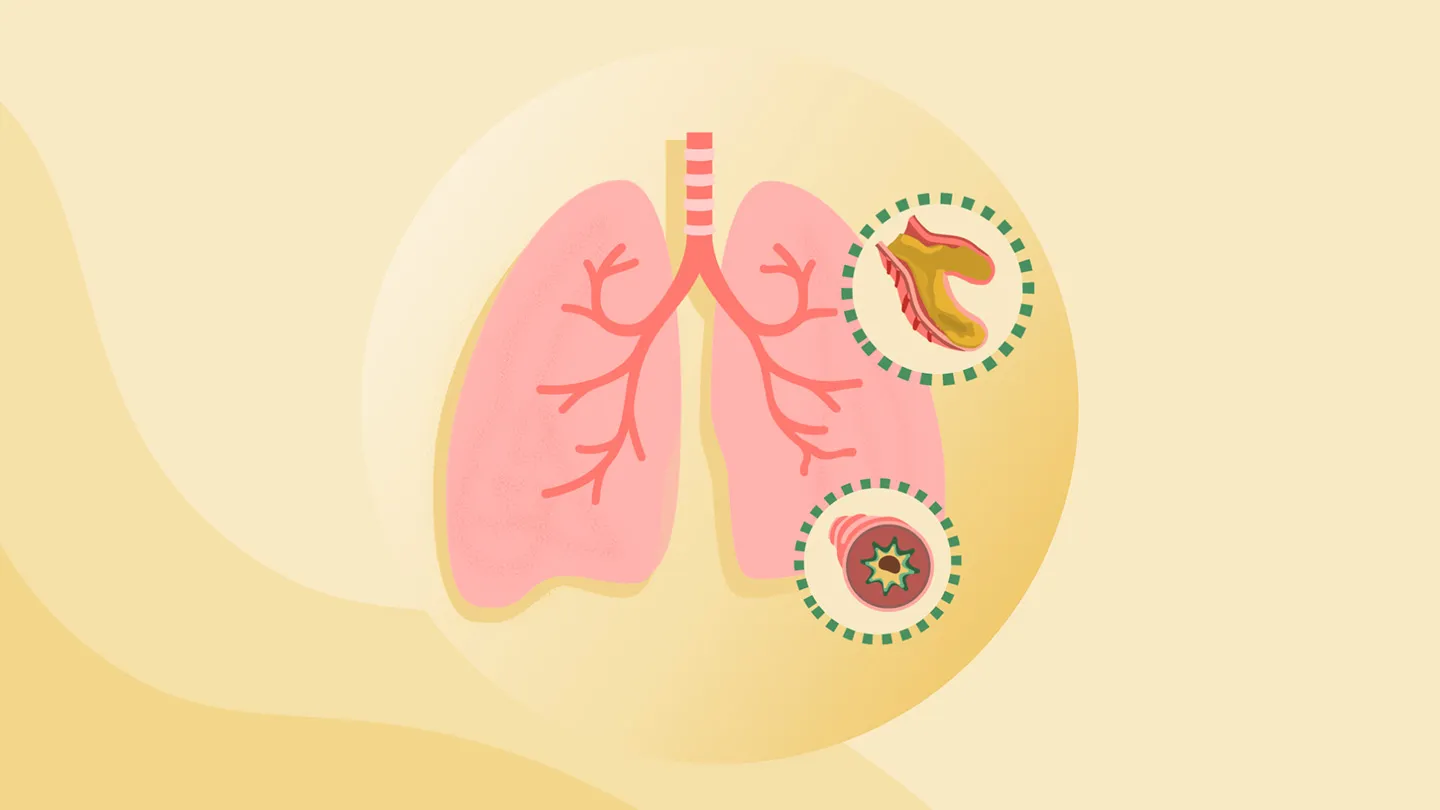

What Is Bronchiectasis?

Bronchiectasis is a continual lung illness through which the airways or bronchi…